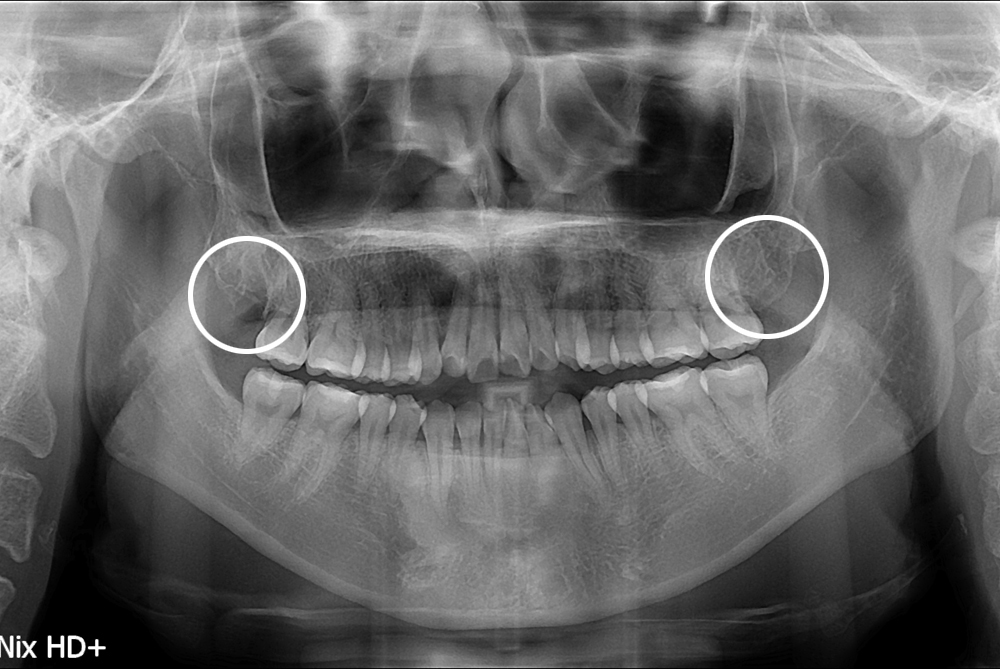

[사랑니] 난발치 사랑니 발치

치료전 : 2017-04-11